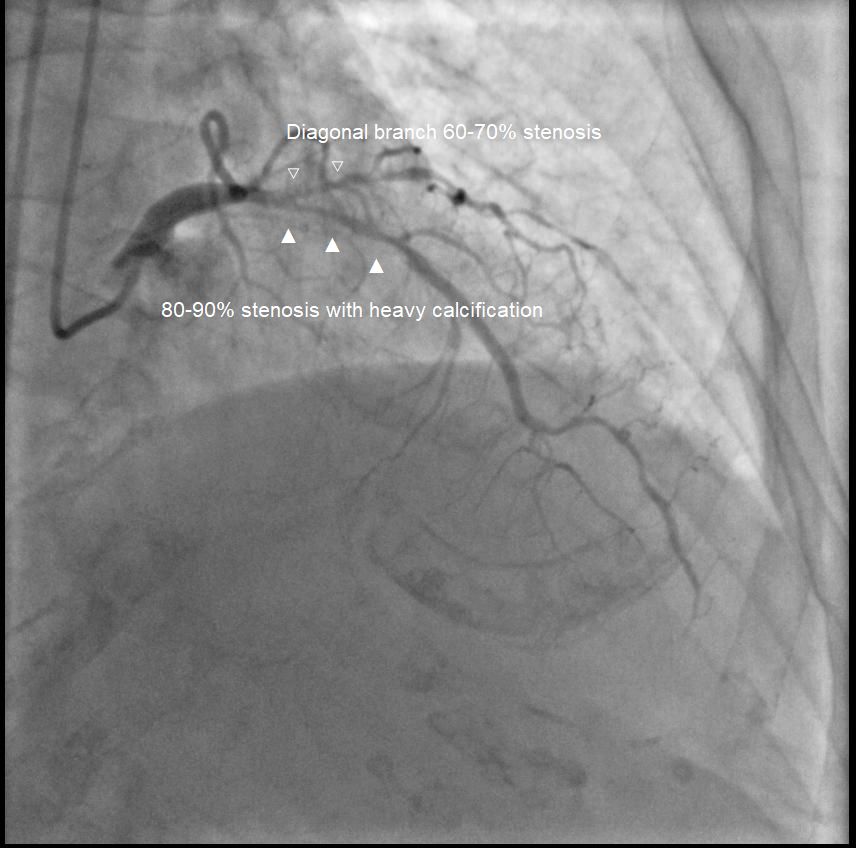

Coronary angiography showed significant stenosis:

Left main 50-60%,

LAD 80-90% (proximal to mid) with heavy calcification, diagonal branch 60-70%,

LCx 90-95% (ostium to proximal),

Left main 50-60%,

LAD 80-90% (proximal to mid) with heavy calcification, diagonal branch 60-70%,

LCx 90-95% (ostium to proximal),